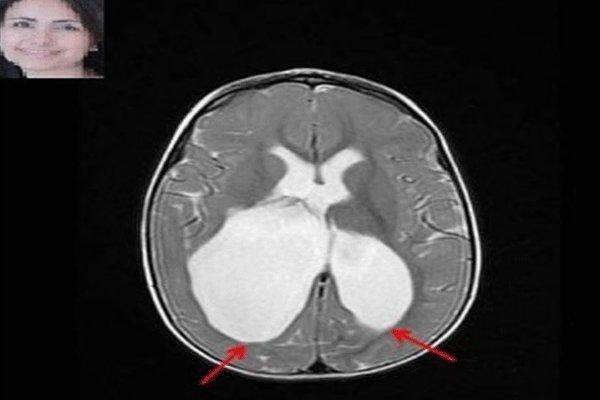

محققان کانادایی به سرپرستی دکتر مریم اسکویی، متخصص مغز و اعصاب بیمارستان بچه ها مونترال کانادا پیروز به کشف عامل ژنتیکی فلج مغزی شدند.

مطالعات محققان نشان می دهد، مولفه های ژنتیکی در بروز فلج مغزی بیش از تصورات پیشین نقش دارند. در این مطالعه به چگونگی تعامل عوامل خطر ژنتیکی نیز پرداخته شده است.

نتایج این مطالعه می تواند باورهای گذشته درباره عوامل فلج مغزی را تغییر دهد زیرا پیش از این تصور می شد عفونت و خفگی هنگام تولد عاملی برای فلج مغزی هستند، به همین دلیل توجهی به آزمایشات ژنتیکی پیش از بارداری نمی شد.